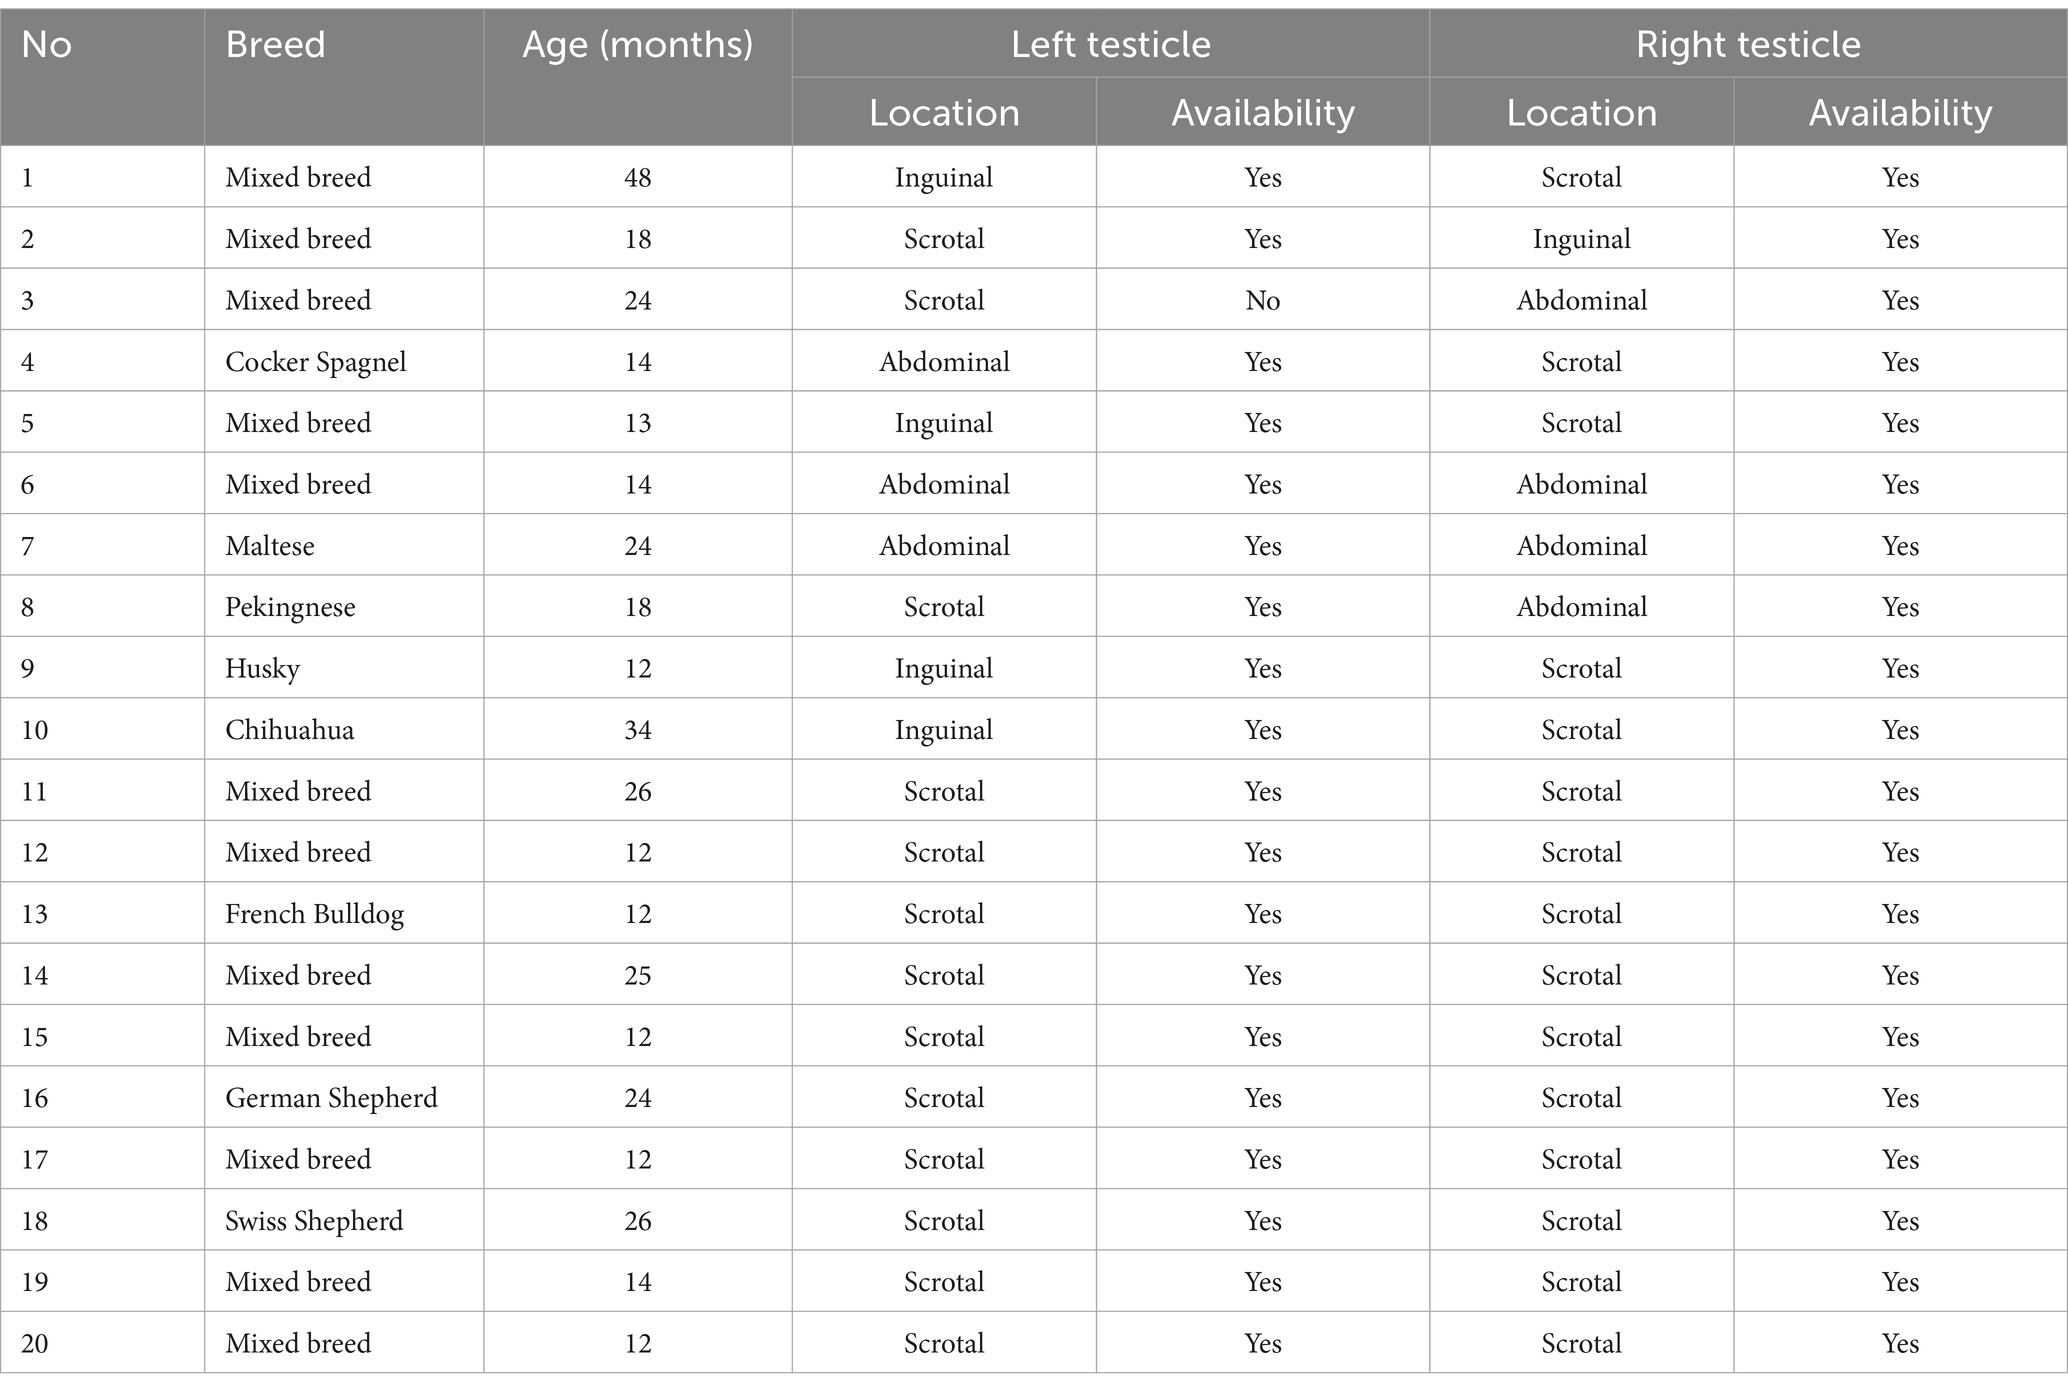

Un total de 50 perros machos de diversas edades y razas fueron reclutados para el estudio. Veinte perros con al menos un testículo retenido fueron clasificados en el grupo CRYPTO. Otros 20 varones intactos con ambos testículos localizados dentro del escroto fueron asignados al grupo INTACT. Además, se incluyeron 10 perros gonadectomizados bilateralmente como controles negativos, formando el grupo CASTRADO. Todos los perros se sometieron a un examen clínico y no se observaron preocupaciones con respecto a su salud general o reproductiva. Los pacientes con criptorquídeas fueron sometidos a exámenes ecográficos para confirmar la posición del testículo retenido antes de cualquier intervención quirúrgica propuesta.

La composición de los tres grupos en términos de edad, raza, estado de criptorquídea unilateral o bilateral y la ubicación del testículo retenido se detalla en la Tabla Suplementaria 1.

Se analizaron secciones aleatorias de ambas gónadas descendidas (DES) del grupo INTACT. También se analizaron todos los testículos retenidos (RET) de los individuos criptorquídeos admitidos. Cuando estaba disponible, se evaluó el testículo contralateral (CONTRA) de las criptorquidas unilaterales. En la Tabla 1 se presenta una descripción detallada de la disponibilidad de muestras para las evaluaciones histológicas e inmunohistoquímicas.